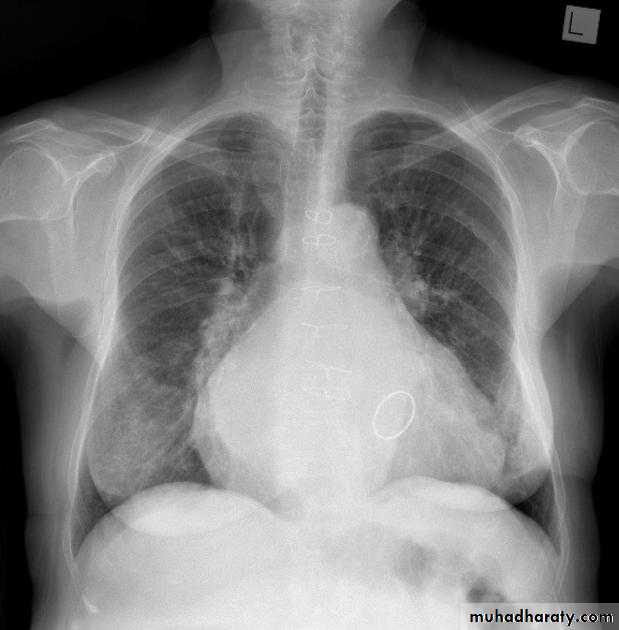

Pericardial effusions occur when fluid collects in the pericardial space (a normal pericardial sac contains approximately 30-50 mL of fluid).

Radiographic features

Plain radiograph

a very small pericardial effusion can be occult on plain film there can be globular enlargement of the cardiac shadow giving a water bottle configuration known as Globe shape heart or pumpkin shape heart

.